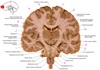

23

Q

a

septum pellucidum

24

b

Body of lateral ventricle

25

c

Corona radiata

26

d

Column of fornix

27

e

Third ventricle

28

f

Anterior commissure

29

g & h

amygdala (nuclear complex)

30

i

globus pallidus internus

31

j

globus pallidus externus

32

k

Putamen

33

L

Internal capsule genu

34

m

head of caudate nucleus

35

n

Anterior tubercle of thalamus

36

o

Body of corpus callosum